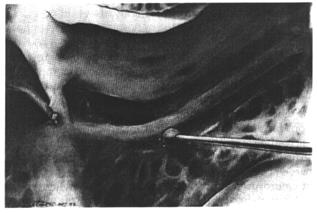

Поскольку кость здесь очень тонка, используется алмазный бор диаметром 1мм. и постоянная ирригация. Малым экскаватором или серповидным ножом удаляются костные пластинки с нерва (рис.38, 39).

| |